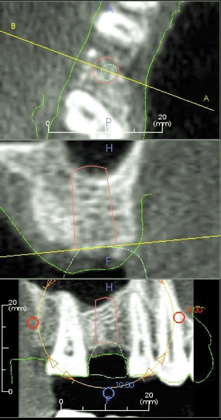

Due to the need for medical treatment for shoulder and neck issues, the patient was delayed in returning to the office for subsequent evaluation. At the 7-month postoperative appointment, the socket was assessed and a panoramic radiograph was taken to evaluate the bone at the planned implant site (Figure 1). The socket was filled with bone that was indistinguishable from the patient's native bone adjacent to the site. Insufficient height to place an implant was noted, which would require a crestal sinus lift prior to implant placement. A cone-beam computed tomography (CBCT) scan was ordered for planning purposes. Planning software was used to properly position a 5.2 x 10 mm implant for placement into the edentulous site, confirming that some elevation of the sinus would be required (Figure 2 and Figure 3). This data was used to order a surgical stent to guide implant placement (Figure 4).

(2.) Virtual planning of the implant to be placed in the edentulous right first molar site.

Figure 2

(3.) Virtual design of the surgical stent to guide the implant placement.

Figure 3